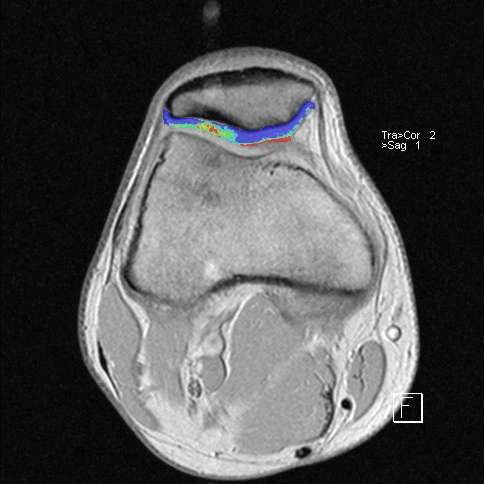

Способ проиллюстрирован чертежами, поясняющими сущность и эффективность заявляемого способа. На фиг.1 - оперативный доступ к сухожилию длинной малоберцовой мышцы в области наружной лодыжки; на фиг.2 - чрезоперативный доступ, теновыделителем проксимально отсекают сухожилие длинной малоберцовой мышцы от мышечного брюшка и выводят сухожилие в область операционной раны; на фиг.3 - отсеченное сухожилие длинной малоберцовой мышцы на препаровочном столике; на фиг.4 - схематично представлено направление проведения каналов, сухожилия и его крепление интерферентными шурупами в мыщелках большеберцовой и бедренной костях, трансоссальная фиксация в головке малоберцовой кости;

на фиг.5 - рентгенограмма коленного сустава в прямой и боковой проекции больного с начальными признаками остеоартроза; на фиг.6 - магнитно-резонансная томография коленного сустава больного, где отсутствует передняя крестообразная связка и наружная боковая связка; на фиг.7 - магнитно-резонансная томография коленного сустава больного, где показана восстановленная передняя крестообразная связка и наружная боковая связка; на фиг.8 - полное сгибание коленного сустава через три месяца после операции; на фиг.9 - стабильность коленного сустава через три месяца после операции.

На МРТ левого коленного сустава после операции в боковой и фронтальной проекциях: 10 - пластическое восстановление ПКС дупликатурой сухожилия длинной малоберцовой мышцы, 11 - пластическое восстановление малоберцовой коллатеральной связки сухожилием длинной малоберцовой мышцы, 12 - интерферентные шурупы (Фиг.7).

Дистрофические изменения суставного хряща надколенника (с использованием опции «картирования хряща»)